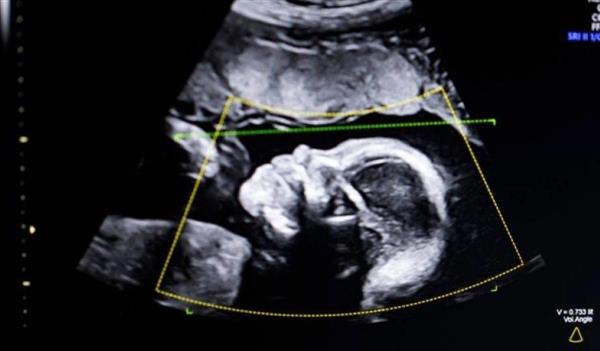

أعلنت إدارة الغذاء والدواء الأمريكية (FDA)عن إجازة استخدام تقنية «Delivery Date AI» التي طورتها شركة «Ultrasound AI»، وهي أول برنامج قائم على الحوسبة السحابية يستخدم الذكاء الاصطناعي للتنبؤ بموعد الولادة بدقة عالية، بالاعتماد فقط على صور الموجات فوق الصوتية القياسية دون الحاجة لقياسات يدوية معقدة.

يأتي هذا الترخيص ليقدم حلًا طبيًا ثوريًا في حالات الحمل التي يصعب فيها تحديد عمر الجنين بالطرق التقليدية، مثل عدم دقة تاريخ آخر دورة شهرية.